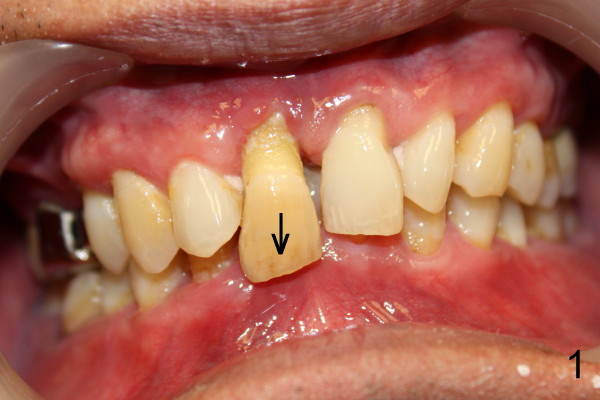

Sixty-one-year-old otherwise healthy man requests extraction of the upper right central incisor, which is mobile and supraerupted (Fig.1 arrow). He denies the history of trauma, although X-ray shows sclerosed canal of the affected tooth (Fig.2 black <, as compared to that of the left central (blue <).